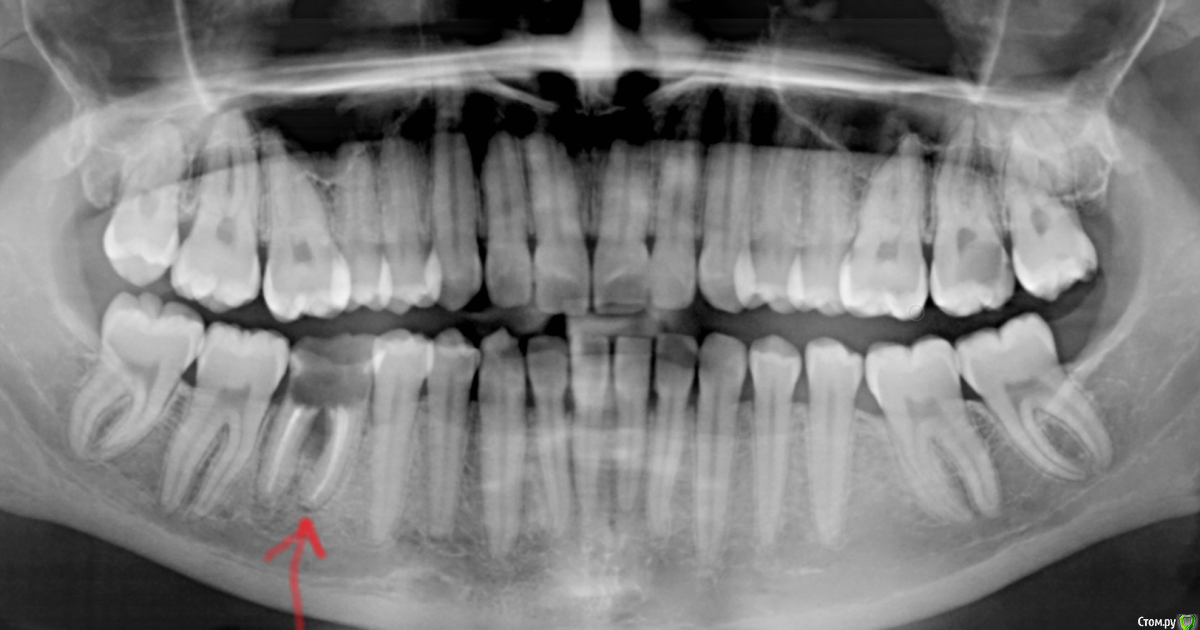

Оксана1318 Опубликовано 26 мая, 2019 Поделиться Опубликовано 26 мая, 2019 Добрый вечер! Подскажите, пожалуйста, у меня полностью разрушился зуб (шестерка на снимке - на нее направлена красная стрелка) полтора года назад. То есть остался только корень, а стенки сломались и выпали. За это время соседние зубы т.е. 5 и 7 не переместились друг к другу вроде бы, хотя же шестерки нет, если не считать корень. Получается корень шестого зуба их пока держит и не дает перемещаться???Я слышала, что организм человека не терпит пустоты и это же касается зубов? Я хочу на днях вырвать этот корень и ставить имплант. Но очень переживаю, что если вырву корень, он больше не будет сдерживать соседние зубы и нужно будет ждать три-четыре месяца перед постановкой импланта, за это время 5-ый и 7-й зуб начнут перемещаться в сторону к друг другу и у меня образовываться начнут расстояния между зубами некрасивые. Возможно ли что за 3-4 месяца перемещение произойдет? Может есть конструкции, которые не дадут этому произойти??? Заранее спасибо! Ссылка на комментарий

krokomot Опубликовано 28 мая, 2019 Поделиться Опубликовано 28 мая, 2019 на период удаления и установки имплантата не стоит беспокоиться о перемещении зубов, срок слишком маленький, по поводу решения вопроса о возможности одномоментной имплантаци сомневаюсь, так как слишком мало заапикальной кости, в любом случае придется сделать томограмму где всё можно измерить в миллиметрах, В случае удаления без установки имплантата следует обязательно проводить мероприятия по консервации лунки, для получения наибольшего объема костной ткани после заживления. Конкретно я в данной ситуации, удалил бы зуб с аугментацией лунки, через 2 месяца установка имплантата и через 2-4 месяца его протезирование. 1 Ссылка на комментарий